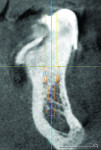

During diagnostic planning procedures, a traditional complete denture is designed and created according to the patient’s esthetic expectations and established restorative space. This diagnostic denture allows the clinician and technician to evaluate the restorative space and function of the proposed implant prosthetic treatment as a team. The diagnostic denture can also be converted to a radiographic stent for CBCT scans. Using these scans, one can plan the intraoral position of the guide pin, thus providing a reference point for vertical dimension and screw access in relation to tooth placement (Figure 1). The problem with using an existing or old denture for case planning and scanning concerns residual ridge resorption, the result of which is that denture teeth are not in their optimal position. The ideal prosthetic tooth position is in line with the vector forces of occlusion to the long axis of implant body. The best way to plan for implant placement and functional occlusion is through the use of a diagnostic denture on a semi-adjustable articulator. The waxed denture tooth arrangement is then processed, finished, and polished to include all of the hard edentulous anatomy that will provide support to the complete denture prosthesis.